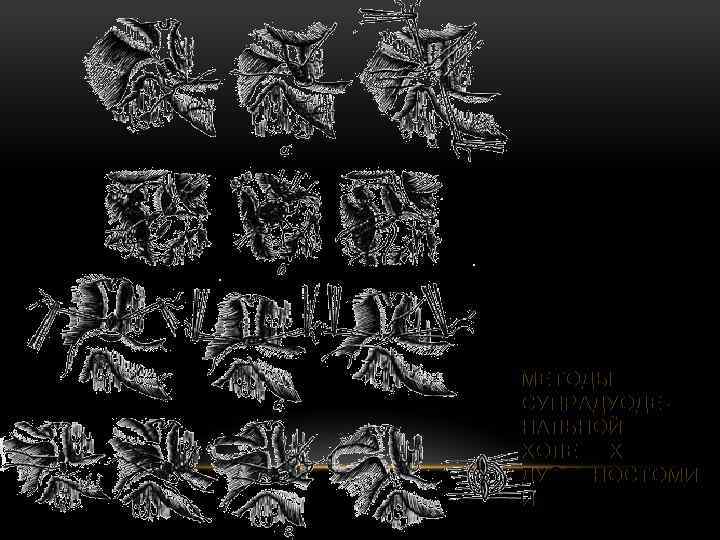

МЕТОДЫ СУПРАДУОДЕНАЛЬНОЙ ХОЛЕДОХОДУОДЕНОСТОМИ И

МЕТОДЫ СУПРАДУОДЕНАЛЬНОЙ ХОЛЕДОХОДУОДЕНОСТОМИ И